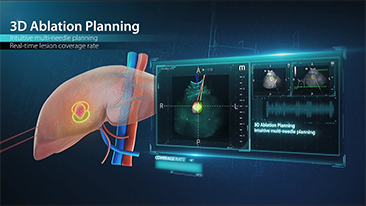

Las soluciones de imĂĄgenes generales de Resona de Mindray ayudan al personal clĂnico a realizar diagnĂłsticos y obtener resultados de tratamiento mĂĄs precisos y eficientes a travĂ©s de sondas para aplicaciones de subdivisiĂłn integrales y herramientas de aplicaciĂłn clĂnica eficientes.